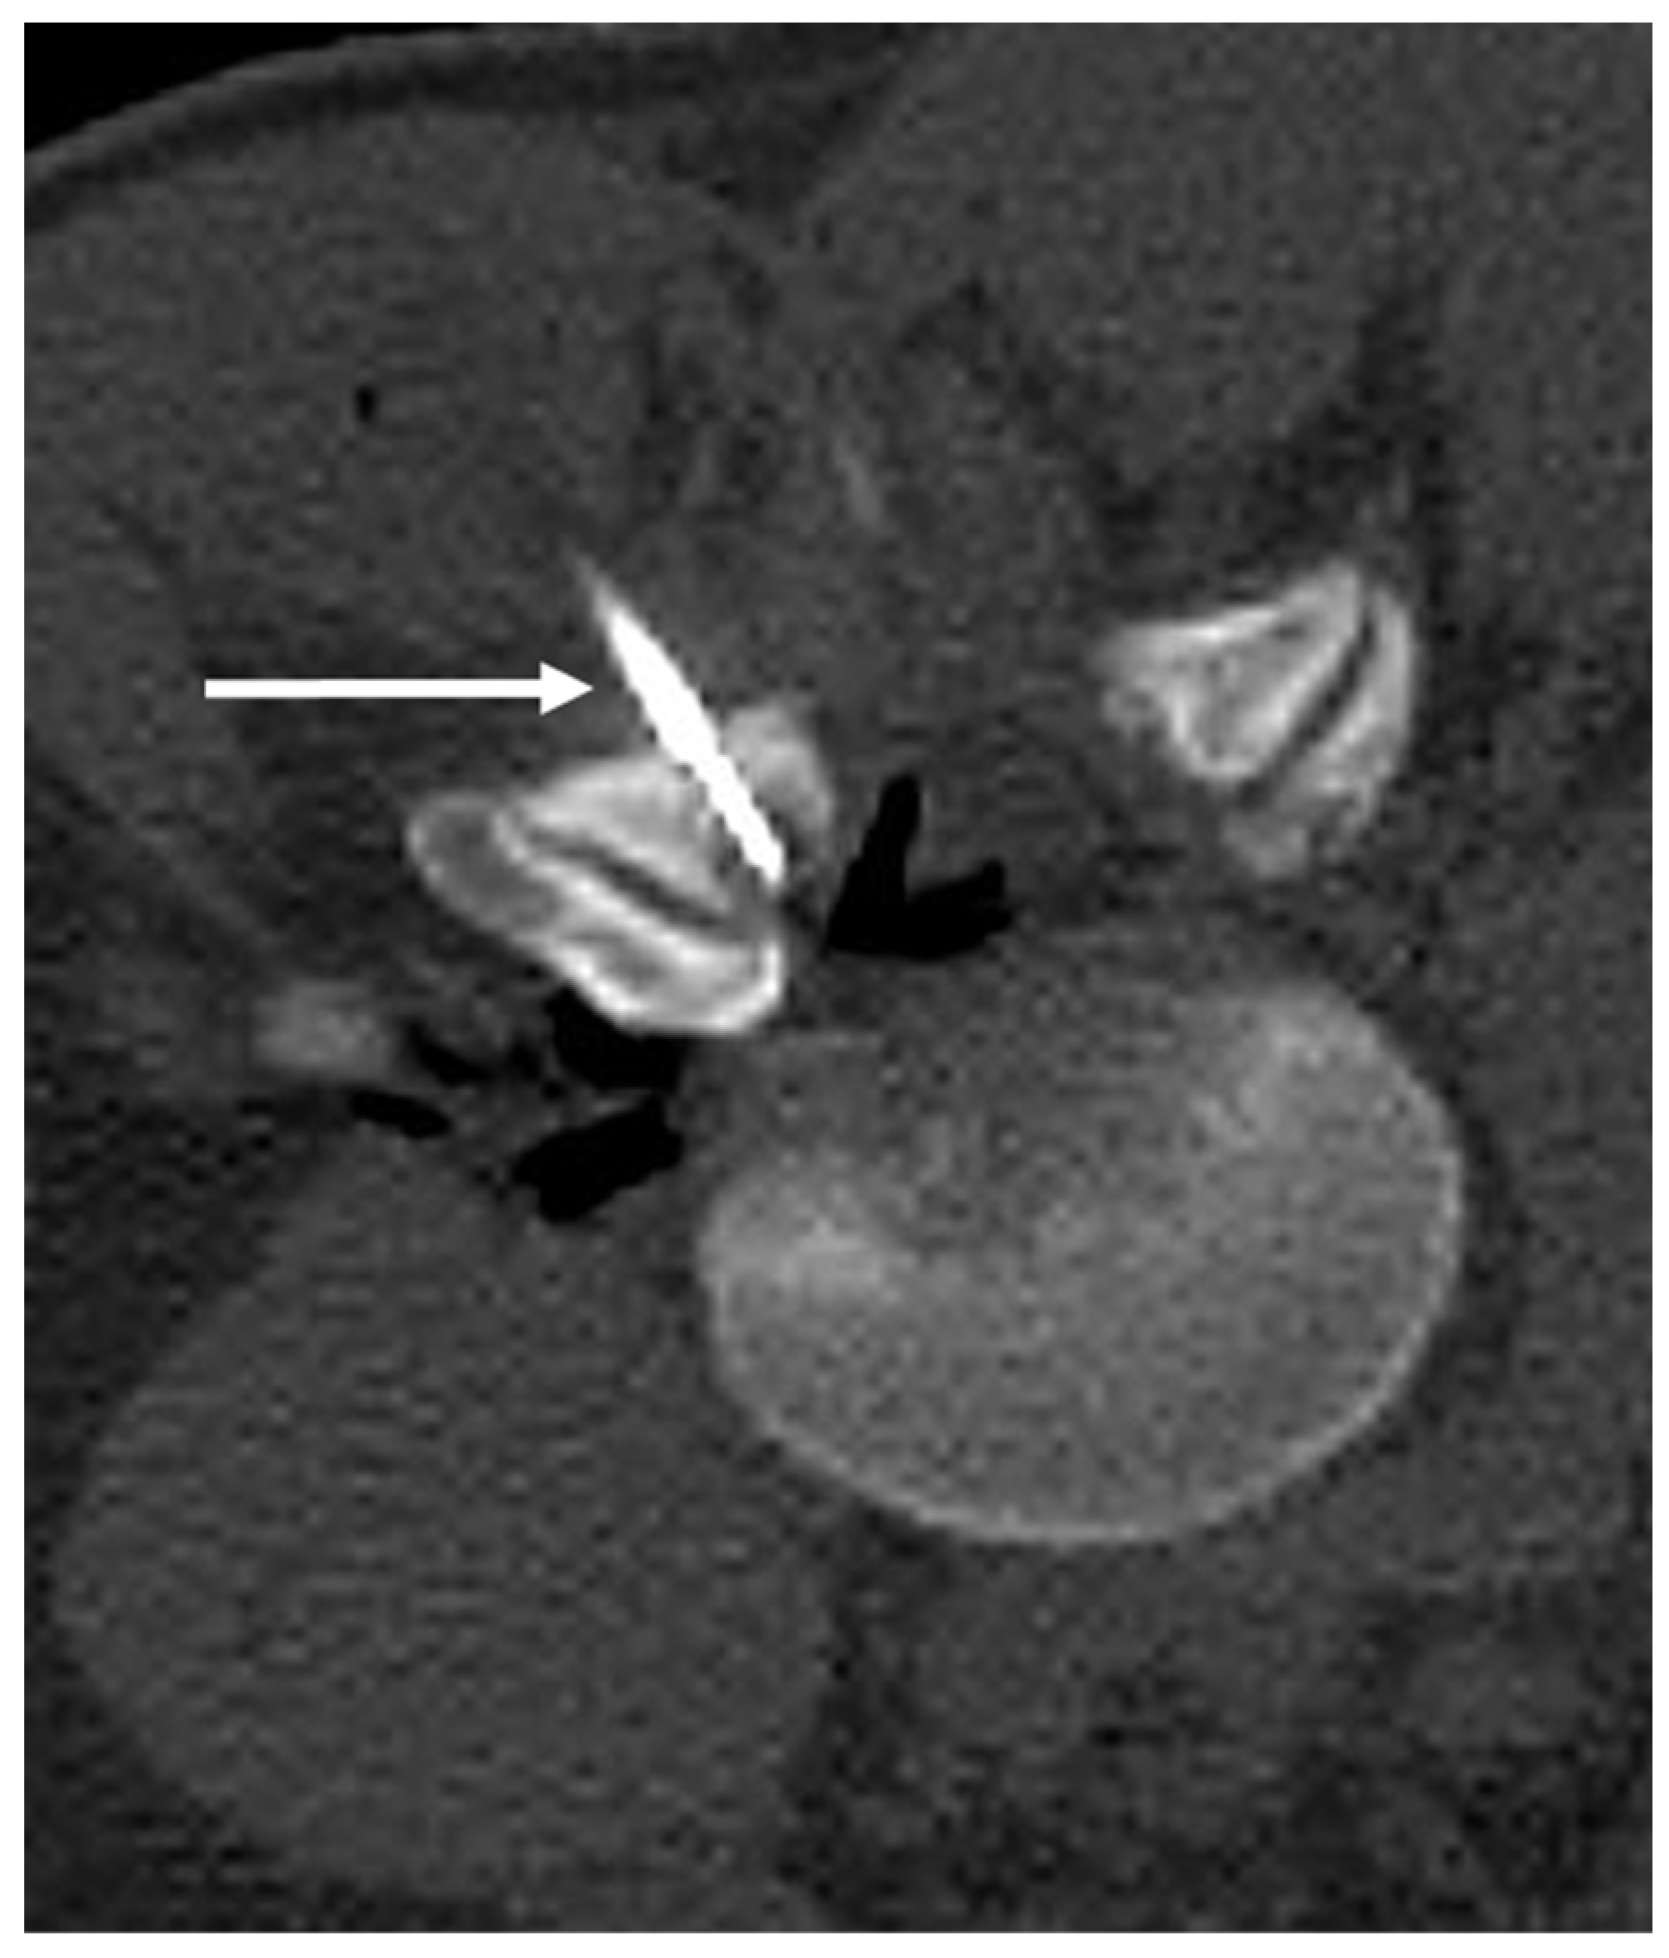

3.2. Osteoid Osteoma

| Osteoid osteoma | Lucent nidus, usually 2–10 mm. May be surrounded by sclerotic rim. | Surrounding marrow oedema on fluid sensitive sequences (best seen on STIR). Nidus can be occult on MRI. |